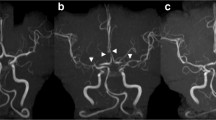

Cortical SAH, ICH, seizures, and reversible posterior leukoencephalopathy often occur within the first week with ischemic complications (stroke and TIA) within the second week [22]. By definition, stenosis improves within 4–12 weeks (Fig. 2).

(a) Catheter angiography at disease onset: multiple narrowing and dilatations, (b) Control catheter angiography at 3 months, (c) MRA at disease onset and (d) Control MRA [22]

Cerebral angiography may show single or multi-vessel narrowing and dilation (“string and beads”) with improvement following intra-arterial calcium channel blockers. As compared to vasculitis, RCVS has a relatively normal CSF profile. While the gold standard for diagnosis is angiography, TCD has been used successfully to show improvement in the blood flow velocities over time, but may underestimate changes in vessel diameter in the acute phase [18, 23,24,25].

Ducros et all looked at TCD in 64 patients with RCVS with 44 (69%) having increased arterial velocities with a mean of 163 ± 27 cm/s in middle cerebral arteries and 148 ± 20 cm/s in carotid siphons. Angiography confirmed multifocal segmental arterial constriction. Twelve patients had serial TCD with a moderate increase in velocities on first TCD (mean 6.8 days) but marked on the second TCD (mean 22.5 days), long after the headache had subsided [22]. Levin et al. also found that TCD flow velocities in the MCA (VMCA) reached a mean peak three to four weeks after headache onset [26]. Another case series reported bimodal peaks with increased velocities at days 15 and 17 [27]. Marsh et al. demonstrated improvement in velocities in seven patients with RCVS, which correlated to initiation of a calcium channel blocker [24].